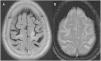

ResultsIn all three cases MRI showed the cortical hypointensity adjacent to the white-matter lesion in the T2-weighted gradient-echo sequence. In the patient with multiple sclerosis, this sign appeared earlier than the abnormal signal in the white matter. The patient being treated with rituximab was diagnosed postmortem and the pathology findings correlated with the MRI findings.

ResultadosEn los tres casos se observa en la RM el hallazgo de hipointensidad cortical adyacente a la lesión de la sustancia blanca en la secuencia EGT2. En la paciente con esclerosis múltiple, este signo fue más precoz que la alteración de señal en la sustancia blanca. El paciente en tratamiento con rituximab fue diagnosticado post mortem y se presenta una correlación radiopatológica.